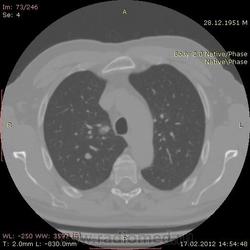

КТ.

В феврале 2012 года при очередном флюрографическом обследовании были обнаружены изменения в лёгких. По собственной инициативе было сделано КТ лёгких.

На первый взгляд - метастазы. А так, если родственник, искать выходы на МСКТ.

Согласен с Андреем Юрьевичем - наиболее вероятно - это метастазы...исключите первичное новообразование почки.

Согласен с коллегами, внешне вылитые метастазы. Но почему нет контраста? Не соли мочевой кислоты точно. Учитывая анамнез можно думать о неопроцессе почек.

Повторяюсь (мнение озвучил еще до КТ и до Ваших коментов) но это отдаленные по времени метастазы рака почки....увы....и даже если будет найден еще один первичный очаг, то все равно это - метастазы...опять - увы....